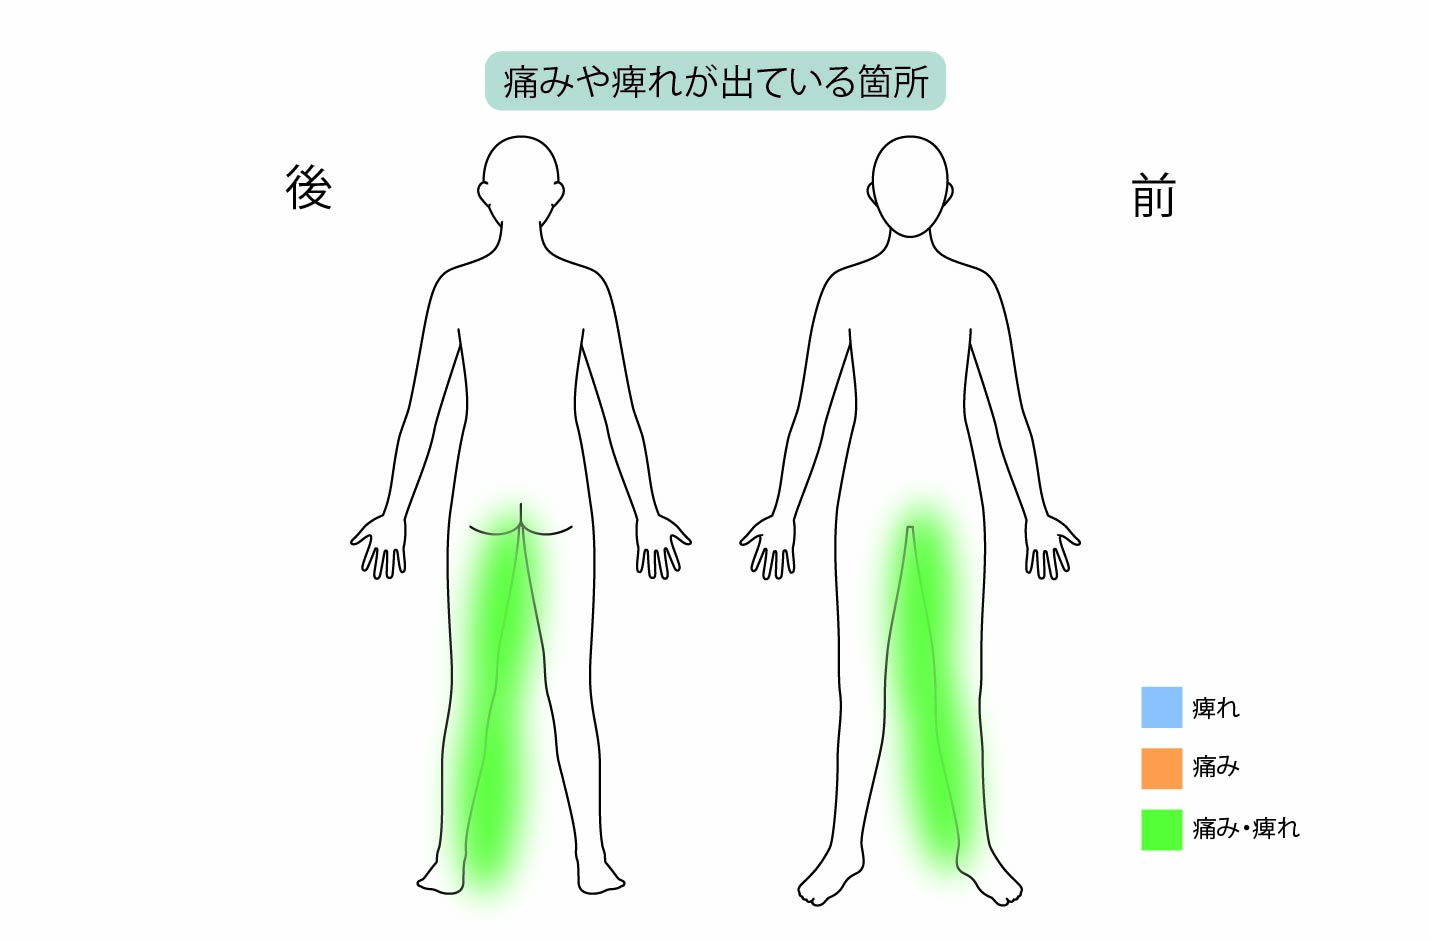

| 症状・疾患 |

| 相談内容 | 1年前から右足先と右殿部の痛み、右下肢の痛みとしびれがあり、他院を受診したところ腰椎MRI検査で「L5分離すべり症」と診断。その医院でL5/S後方固定除圧術(ボルトの手術)を施行されたとのことです。術後、右足外側の痛みはよくなったとのことだったのですが、右下肢内側の痛みとしびれが悪化して改善しないので当院を受診されました。来院時から治療方法は日帰り手術を希望されていました。 |

| 診察結果 | MRI画像を確認したところ、他院で手術を行ったL5/Sの除圧範囲は問題ありませんでした。しかし「右椎間孔狭窄(L4/5)」を確認し、右下肢内側の痛みと痺れは右L4神経根の症状と一致。そのためL4/5の神経圧迫が、症状の根本原因だと考えました。 また診断を進めると右下肢内側の痛みとしびれは、他院で行った後方固定除圧後の合併症である「隣接椎間障害」によるものでした。 |

| 治療内容と方針 | 右下肢内側の痛み、しびれは後方固定除圧後の合併症である隣接椎間障害によるもので、右L4/5椎間孔の狭窄症が原因だったので「PEL(脊柱管狭窄症内視鏡下術)」を実施。神経を圧迫している骨をドリルで削開しました。削開後は、椎間孔狭窄の圧迫が取れて右L4神経根が確認できました。 それと同時に、神経修復作用の効果を期待できる血小板由来の成長因子を注入する「PRP療法」を行いました。 なお、他院で手術したL5/Sの部位は再発がないので、そこの部位の治療は行っていません。 |

| 治療後の経過 | 主症状であった右下肢内側の痛みとしびれは治療後、下肢痛みが無くなり、しびれの範囲も狭くなり徐々にとれていきました。 術後1ヶ月後と3ヶ月後には、レントゲンを見ながら神経修復に効果的なPRPを注射しております。 ご本人は、他院で手術を行ってその後痛みが悪化して内服加療で改善できず諦めていたそうです。治療後は右下肢のいたみがとれてウォーキングができるようになったとのことです。 |